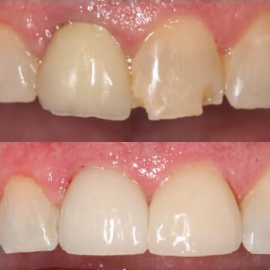

Implant supported teeth

Implant bridge

Single tooth implant